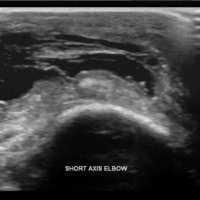

Olecranon bursitis refers to inflammation of the olecranon bursa. The olecranon bursa is a subcutaneous space lined with a synovial membrane that secretes fluid to provide smooth and almost frictionless motion between the skin, the subcutaneous tissues, and the olecranon. Because of its superficial location, it is a common site for injury, inflammation, and infection. Repeated traumatization of the elbows at work led to common terms for different forms of occupational bursitis such as “student's elbow” or “miner's elbow”.

Approximately one third of the cases of olecranon bursitis are septic. Many patients with septic olecranon bursitis lack a history of trauma or a visible injury over the olecranon.

Lateral radiograph of the elbow reveals soft tissue swelling superficial to the olecranon. Ultrasound may show a fluid collection in the olecranon bursa, features of synovial proliferation and/or hyperemia.

CT will show fluid density at the subcutaneous tissue superficial to the elbow. Bursal fluid collection in MRI has the following features: hypointense-T1, mainly hyperintense-T2, and enhancement of bursal margins in post contrast imaging.